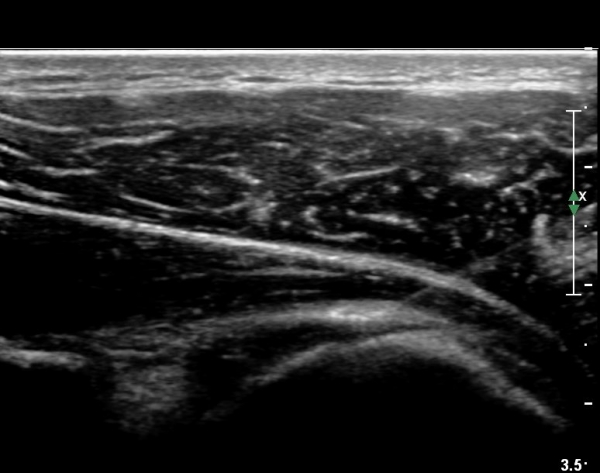

º¸¿© °ß°©ÇÏ±Ù°Ç ÆÄ¿­ÀÌ ÃßÁ¤µÈ´Ù(»çÁø 1). ŽÃËÀÚ¸¦ ¾à°£ ¾Æ·¡·Î À̵¿ÇÑ ÈÄ

ÆÈÀ» ¿ÜȸÀüÇϸ鼭 °üÂûÇÏ´Ï °ß°©ÇÏ±Ù°Ç ÆÄ¿­ÀÌ ¶Ñ·ÈÇÔ(»çÁø 2, 3).